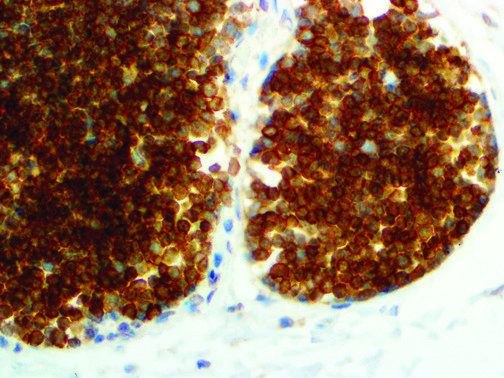

It is the ICU physician who is most likely to witness one of the deadliest manifestations of the abnormal immunological response, the cytokine storm syndrome (CSS). This response is also referred to by some as the cytokine release syndrome (CRS). CSS is characterized by continuous activation and expansion of macrophage and lymphocyte populations, which secrete large amounts of cytokines, causing the cytokine storm. This massive cytokine release is akin to hemophagocytic lymphohistiocytosis (HLH) disease, a syndrome characterized by initial unchecked and persistent activation of cytotoxic T lymphocytes and NK cells.

Clinical and laboratory manifestations of HLH include fever, enlarged liver and/or spleen, neurologic dysfunction, coagulopathy, liver dysfunction, cytopenias (i.e., low levels of erythrocytes, leukocytes, and/or platelets), hypertriglyceridemia, hyperferritinemia, hemophagocytosis, and eventually diminished NK cell activity as the immune system becomes progressively paralyzed. HLH can be familial (primary HLH) or secondary to another disease process (sHLH), such as rheumatic disease, in which it is referred to as macrophage activation syndrome (MAS, characterized by elevated ferritin).